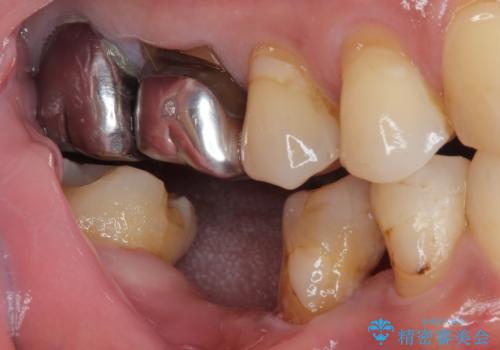

- 奥歯を抜歯してから放置しているとのことで来院された患者様です。

地元の歯科医院では、インプラント補綴治療かブリッジによる治療の二択を提示され、悩んでいらっしゃる状態でした。

歯が割れて抜歯になってしまったとのことと、ブリッジの土台となる手前の歯は既に神経が取り除かれていて、こちらも破折するリスクが高いことから、咬合力に抵抗できるよう、インプラントによる補綴治療を行うこととしました。

手前の神経を取り除いている歯も、合わせて補綴治療を行うこととしました。